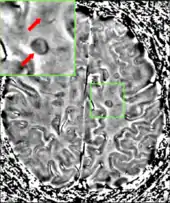

Animation showing dissemination of brain lesions in time and space as demonstrated by monthly MRI studies along a year

Multiple sclerosis as seen on MRI

Clinical data alone may be sufficient for a diagnosis of MS if an individual has had separate episodes of neurological symptoms characteristic of the disease.[53] In those who seek medical attention after only one attack, other testing is needed for the diagnosis. The most commonly used diagnostic tools are neuroimaging, analysis of cerebrospinal fluid and evoked potentials. Magnetic resonance imaging of the brain and spine may show areas of demyelination (lesions or plaques). Gadolinium can be administered intravenously as a contrast agent to highlight active plaques and, by elimination, demonstrate the existence of historical lesions not associated with symptoms at the moment of the evaluation.[53][54] Testing of cerebrospinal fluid obtained from a lumbar puncture can provide evidence of chronic inflammation in the central nervous system. The cerebrospinal fluid is tested for oligoclonal bands of IgG on electrophoresis, which are inflammation markers found in 75–85% of people with MS.[53][55] The nervous system in MS may respond less actively to stimulation of the optic nerve and sensory nerves due to demyelination of such pathways. These brain responses can be examined using visual- and sensory-evoked potentials.[56]